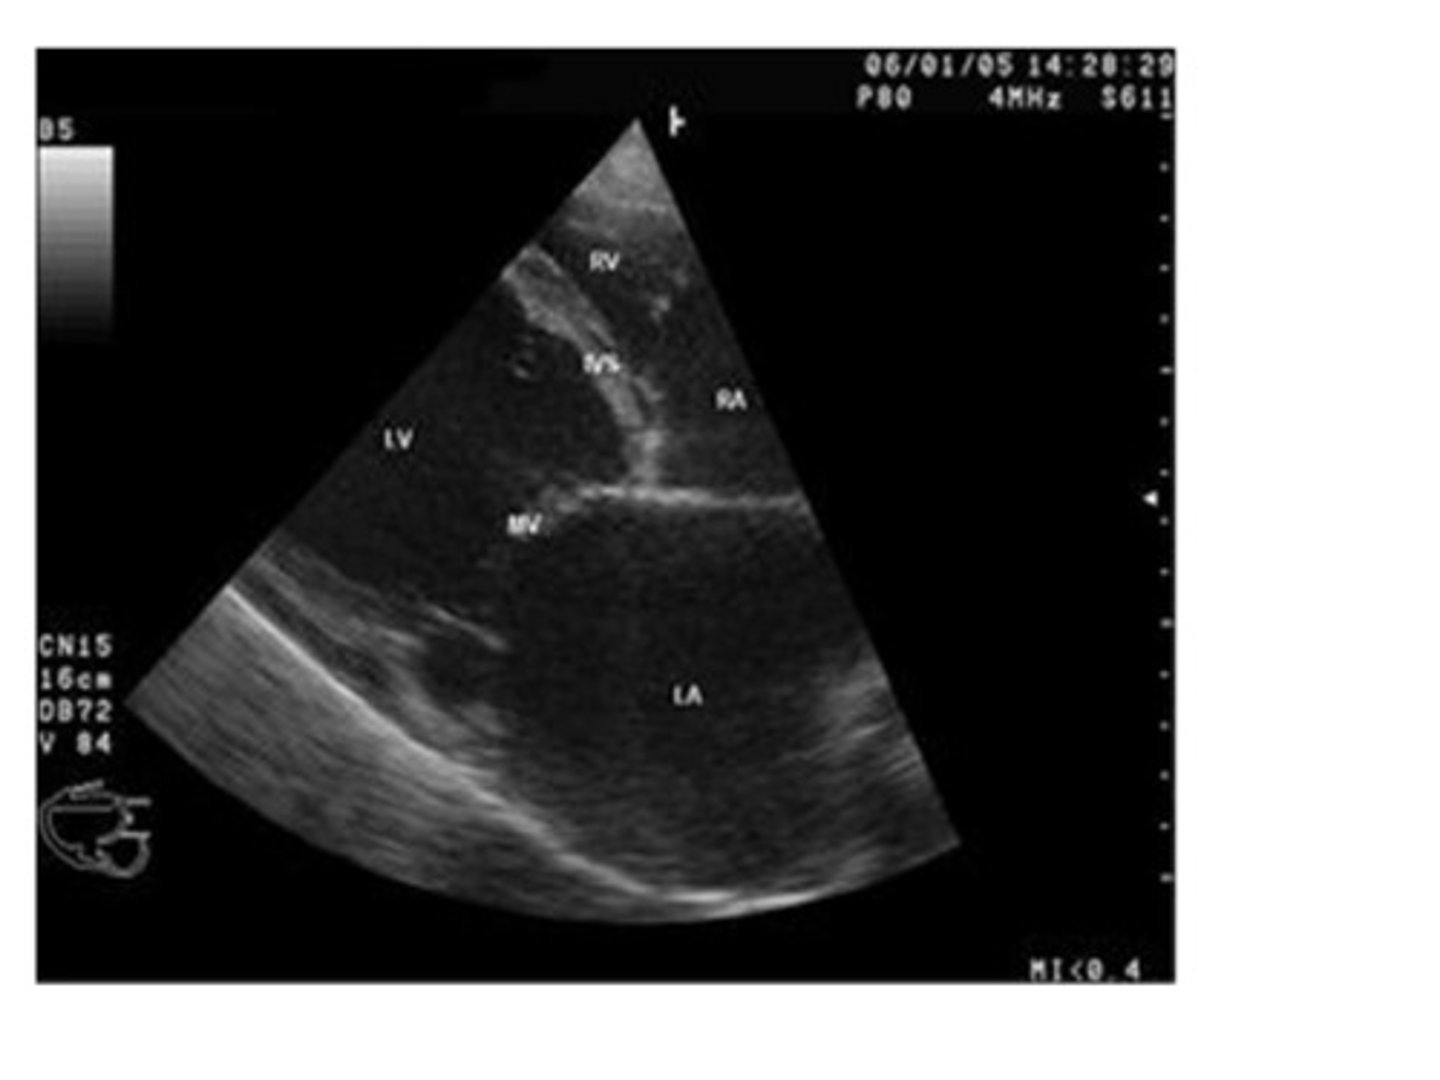

Referencing the image to the right, which imaging mode is illustrated and what function is demonstrated?

Doppler mode illustrating blood flow through the heart

Spectral Doppler mode illustrating flow velocities

Gray scale mode illustrating heart valve motion

M-mode illustrating heart wall motion and heart valve motion